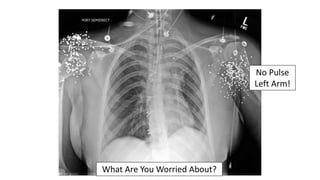

What Are You Worried About?

No Pulse

Left Arm!

Gunshot Wound

To The Neck…

Injury To The Trachea & Esophagus

• Shot gun blast – pulseless left arm